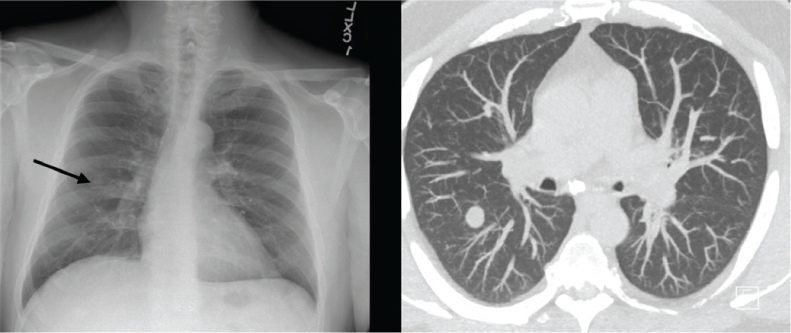

Before presentation at our institution, the patient developed progressive dry cough and pain while swallowing, with no new neurologic symptoms. A chest CT revealed multiple pulmonary nodules (Figure 1). Several months later, repeated chest CT showed growth of the largest nodule, triggering an evaluation for malignancy. After a failed bronchoscopy attempt, the patient opted for further investigation at our institution. He was first seen by infectious disease specialists at our institution 3 years after fingolimod initiation and was admitted to the hospital, during which time he underwent a bronchoscopy with bronchoalveolar lavage and distal airway evaluation. During hospitalization, he was afebrile, with normal hepatic and kidney function and a normal white blood cell count of 47,000/mm3, with a low absolute lymphocyte count of 680/μL (reference range, 800–3300/μL). Bronchoalveolar lavage cell count, bacterial culture, viral smears, and fungal and acid-fast bacilli analysis and culture were performed. Serum cryptococcus and aspergillus antigens, along with histoplasmosis, blastomyces antibodies, and urine histoplasma antigen were evaluated. His test results were positive for the cryptococcus antigen in serum (1:80 titer) with rare Cryptococcus neoformans in fungal culture from bronchoalveolar lavage. Results of acid-fast bacilli, bacterial, and viral testing were negative. Histoplasmosis antibodies in serum were positive, with a 1:8 titer and negative urine histoplasma antigen. The CSF studies were unrevealing, with no nucleated cells, a glucose level of 55 mg/dL, and a mildly elevated protein level of 66 mg/dL. The CSF fungal culture was negative for Cryptococcus neoformans or Cryptococcus gattii antigen.

Chest radiograph and chest computed tomographic scan showing multiple pulmonary nodules